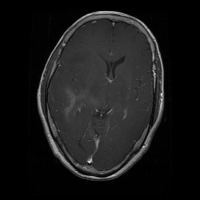

This project has created a labeled MRI brain tumor dataset for the detection of three tumor types: pituitary, meningioma, and glioma. The dataset contains 2443 total images, which have been split into training, validation, and test sets. The training set has 1695 images, the validation set has 502 images, and the test set has 246 images.

- Image types: MRI scans

- Pituitary tumor

- Meningioma tumor

- Glioma tumor

- No Tumor

- The images have been labeled by medical experts using a standardized labeling protocol.

- The labels include the type of tumor and the location of the tumor.